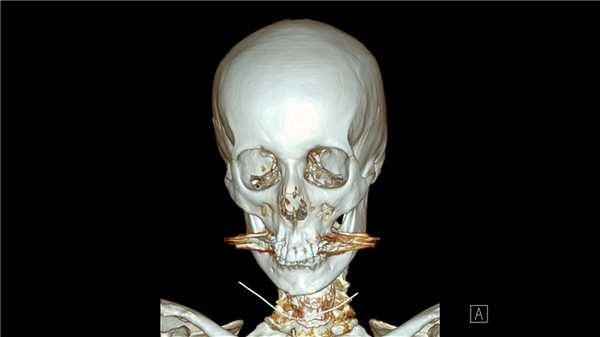

Компьютерная томография (КТ, или МСКТ) является наиболее информативным методом визуальной оценки посттравматических изменений костей, суставов и окружающих тканей. В отличие от других видов лучевой диагностики, при КТ тело человека сканируется поперечно тонкими срезами, на сканах визуализируются ткани различной морфологической структуры (кости, внутренние органы, системы кровообращения и лимфотока), а на основании полученных изображений создается трехмерная модель-реконструкция исследуемой части тела и сканы в трех плоскостях.

Таким образом, будучи пространственным, а не плоскостным (как рентген) методом визуализации любых костных анатомических структур, КТ позволяет достоверно определить тип травмы, увидеть возможные осложнения и повреждения соседних тканей. Поэтому среди врачей это исследование считается предпочтительным для диагностики переломов, особенно осложненных, в том числе внутрисуставных, не рутинных. Плюсом КТ также является оперативность и простота обследования для пациента.

Компьютерная томография позволяет детально визуализировать кости, суставы и окружающие ткани в режиме 3D, что делает этот метод идеальным для диагностики переломов разной степени сложности. Врач-рентгенолог увидит даже небольшое смещение костей, сколы и трещины, а также сможет точно рассчитать любые отклонения с помощью программного обеспечения. На трехмерной реконструкции отсутствуют артефакты (искажения), так что врач сможет точно и достоверно описать результат в заключении.

На КТ в высоком разрешении будут видны деструктивные и воспалительные процессы в костях, суставах и, что не менее важно, в прилегающих тканях. Квалифицированный врач-травматолог, хирург или другой специалист сможет не только ознакомиться с письменным заключением, но и изучить КТ-сканы.

На томограммах в трех проекциях можно рассмотреть позвонки, увидеть, не повреждены ли отростки, нет ли компрессии (сдавления позвоночного канала).

Рентгеновские лучи обладают высокой разрешающей способностью, а данные КТ записываются и обрабатываются на компьютере в высоком качестве. Это делает компьютерную томографию прецизионным и наиболее предпочтительным методом оценки костей и суставов после травм или перед операциями позвоночнике. Стандартная рентгенография — это плоскостное двухмерное изображение, уступающее данным сканирования на современном мультиспиральном томографе. КТ будет наиболее информативна в случае с диагностикой инфекционно-воспалительных процессов (остеомиелита), опухолей и костно-деструктивных процессов.